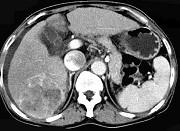

问题 女性,55岁,曾患乙肝,肝硬化多年,右上腹胀痛1月余,CT检查如图所示,最可能的诊断是 ( )

选项 A.肝硬化腹水、下腔静脉血栓形成 B.肝硬化腹水、胆管细胞癌 C.肝硬化腹水、肝癌并下腔静脉癌栓 D.肝硬化腹水、肝脓肿 E.肝硬化腹水、肝血管瘤

答案 C